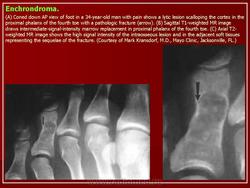

Хондромы

Хондромы являются по морфологическому строению истинными опухолями. Они обладают свойствами присущими опухолям - способностью к прогрессивному росту, рецидивируют. Признаются доброкачественными опухолями, т. к. не метастазируют в отдаленные органы, растут чрезвычайно медленно, нередко годами и даже десятилетиями, заметно не увеличиваясь в размерах. Хотя нет морфологических критериев, которые давали бы основание отличать хондрому одной локализации от другой, локализация в пределах скелета сказывается весьма существенно на клиническом течении хондром. Так, если хондромы коротких трубчатых костей, особенно фаланг кисти не озлокачествляются или озлокачествляются настолько редко, что такие наблюдения описываются как казуистические, то хондромы таза, лопатки, грудины, проксимального отдела бедренной или плечевой костей, озлокачествляются весьма часто. Поэтому больных с хондромами этих локализаций необходимо оперировать также радикально, как и больных с хондросаркомами. Морфологически отдифференцировать хондрому от хондросаркомы высокой степени зрелости нередко затруднительно даже для морфологов высокой квалификации, специально изучающих костную патологию. Подозрение на озлокачествление такого образования может вызвать только четко выраженный рост опухоли, разрушающий окружающую ткань, что наблюдается чрезвычайно редко.

Источником роста хондромы могут явиться нормально расположенный хрящ (суставной, ростковый) и участки дистопированного хряща, а также очаги неокостеневшего эмбрионального хряща. Наиболее часто хондромы встречаются у детей в возрасте 11 -16 лет. Как и все первично-доброкачественные новообразования, хондрома характеризуется солитарным очагом в одной кости. Множественные хондромы, как правило, вторичны и сопровождают диспластический процесс.

Хондромы не всегда имеют четкие границы с окружающей костной тканью. При распространении за пределы кости они отграничены от окружающих мягких тканей тонкой скорлупой, которая местами может не определяться, но обязательно выявляется у основания кортикального слоя. Могут быть обнаружены вкрапления извести. Окружающая хондрому кость несколько уплотнена, на фоне очага видны известковые включения.

Хондрома.

Хондрома.

https://radiopaedia.org/articles/enchondroma